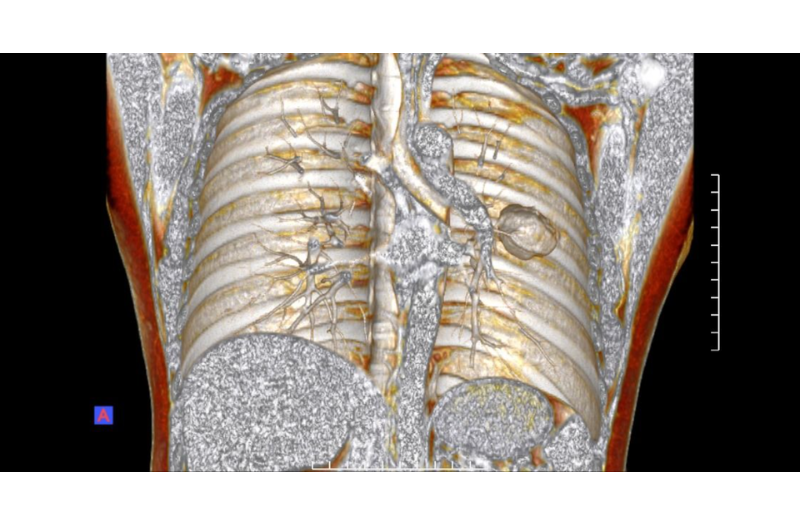

Hình ảnh chụp trên CLVT của bệnh nhân

Hình ảnh cắt lớp vi tính cho thấy khối tổn thương trong gan có cấu trúc không đồng nhất, bên trong có các vùng hoại tử và xuất huyết. Sau tiêm thuốc đối quang từ, tổn thương có hiện tượng tăng ngấm thuốc không đồng đều, trong khi một số vùng hoại tử không bắt thuốc.

Những đặc điểm này gợi ý một khối u ác tính giàu mạch máu – một đặc điểm thường gặp trong choriocarcinoma di căn.